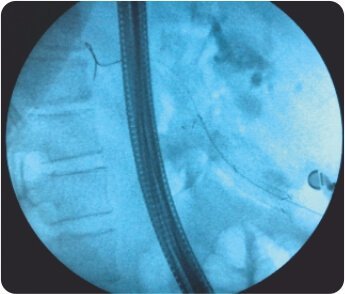

CBD এর EUS নির্দেশিত পাংচার ডুডেনামের প্রথম অংশ থেকে করা হয়েছিল। কোল্যাঞ্জিওগ্রামের পরে, ট্র্যাক্টটি সিস্টোটোম দিয়ে ক্রমান্বয়ে 10 ফারেনহাইট পর্যন্ত প্রসারিত করা হয়েছিল এবং একটি 60x10 মিমি সম্পূর্ণ আচ্ছাদিত বিলিয়ারি স্টেন্ট স্থাপন করা হয়েছিল যা D1 এবং CBD এর সাথে সংযোগ স্থাপন করে। একটি 7F 7cm ডবল পিগটেল প্লাস্টিক বিলিয়ারি স্টেন্ট মেটাল স্টেন্টের মধ্যে স্থাপন করা হয়েছিল যাতে এর স্থানচ্যুতি রোধ করা হয়। কোন পেরিপ্রোসিডারাল জটিলতা ছিল না। এক সপ্তাহের মধ্যে তার বিলিরুবিন স্বাভাবিক হয়ে যায় এবং তাকে কেমোথেরাপি করা হয়।

D1-এ FCSEMS-এর সাথে প্লাস্টিক স্টেন্ট